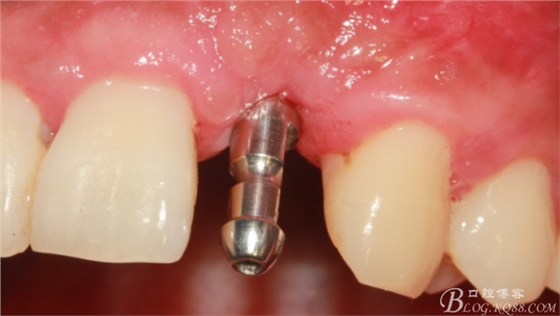

術(shù)后1個(gè)月。

術(shù)后5個(gè)月。

取模。

骨高度穩(wěn)定。